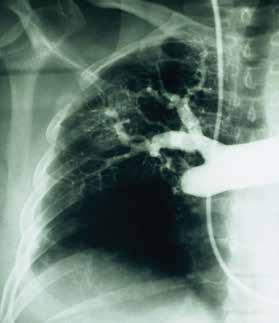

Chronic Thromboembolic Pulmonary Hypertension

There are several categories of pulmonary hypertension. WHO Group I includes patients with idiopathic pulmonary hypertension, familial pulmonary hypertension, drug and toxin related (fen-phen) portopulmonary hypertension, HIV related pulmonary hypertension and pulmonary arterial hypertension associated with connective tissue disorders (such as scleroderma). WHO Group II pulmonary hypertension is often referred to as pulmonary venous hypertension. This includes patients with left ventricular systolic or diastolic dysfunction or valvular heart disease. Essentially, the WHO Group II category includes patients who have an elevated pulmonary capillary wedge pressure and/ or elevated left ventricular end diastolic pressure. WHO Group III pulmonary hypertension consists of patients with COPD, interstitial lung disease, or other conditions in which hypoxia causes vasoconstriction. The remainder of this article will focus on WHO Group IV pulmonary hypertension (chronic thromboembolic pulmonary hypertension or CTEPH). Although WHO Group IV patients are relatively rare, it is crucial to identify them because this is the only type of pulmonary hypertension which is potentially surgically curable.

After acute pulmonary embolism, most patients will recover and have normal pulmonary hemodynamics, gas exchange, and exercise tolerance. It is believed that 1-4% of patients with acute pulmonary embolism will go on to develop CTEPH within two years. It is not clear why some patients with acute pulmonary embolism develop CTEPH. Risk factors include hypercoagulable states, myeloproliferative syndromes, splenectomy and chronic indwelling central venous catheters. Patients with CTEPH present with dyspnea, which can have a gradual onset. Many patients with CTEPH will not have a known previous diagnosis of acute pulmonary embolism. As with other patients with pulmonary hypertension, patients with CTEPH may not show findings on physical exam until pulmonary hypertension is in the late stages. Findings include a right ventricular lift, jugular venous distention, fixed splitting of the second heart sound, hepatomegaly, ascites, and peripheral edema. Patients with CTEPH may have “flow murmurs” heard over the lung fields because of turbulent flow through partially obstructed or recanalized pulmonary arteries. These tend to be accentuated during inspiration.

Acute pulmonary embolism is the trigger for CTEPH. In some patients this triggers a small vessel vasculopathy (for unclear reasons) that contributes to the extent of pulmonary hypertension. This may explain why up to 35 percent of patients who undergo succesful pulmonary thromoendarterectomy can have some degree of postoperative pulmonary hypertension.

Although VQ scanning has become less commonly used for diagnosis of acute pulmonary embolism this remains the initial imaging study of choice in patients with pulmonary hypertension

to separate “small vessel” variants (Idiopathic pulmonary arterial hypertension) from “large vessel” disease (CTEPH) A normal VQ scan essentially excludes the diagnosis of CTEPH. A scan with one or more mismatched segmental defects is suggestive of the diagnosis. However, it is important to note that VQ scan can often understate the extent of central pulmonary vascular obstruction. Once the VQ scan is found to be abnormal then further testing should be undertaken (such as CT angiogram and/or pulmonary angiography). The angiographic findings in CTEPH are distinct from those of acute pulmonary embolism. They can include pouch defects and pulmonary artery webs. Patients with severe pulmonary hypertension have been found to tolerate performance of angiography as well as VQ scan without significant complication rate.

The surgery for CTEPH is quite different from surgical intervention for an acute pulmonary embolism. Surgery for CTEPH is called a pulmonary thromboendarterectomy (PTE), which requires median sternotomy and cardiopulmonary bypass. It requires an often tedious intimal dissection of fibrotic recannalized thrombus from the native pulmonary arterial wall. IVC filter placement is usually recommended before pulmonary thromboendarterectomy. These patients can have a complicated postoperative course and this type of surgery is only done at a few specialized centers in the country. The center which is best known for this type of surgery is the University of California (San Diego). Patients who have undergone PTE are typically maintained on lifelong anticoagulation. To be a candidate for this surgery, a patients must have central, surgically accesible chronic thromboemboli. A significant postoperative complication is pulmonary artery steal, which refers to redistribution of pulmonary arterial blood flow from well-perfused segments into the newly opened segments resulting in ventilation perfusion mismatch and hypoxia. This redistribution of flow resolves over time. Approximately, 30% of PTE patients can develop reperfusion pulmonary edema. The perioperative mortality of pulmonary thromboendarterectomy can be in the range of 2-3% in experienced centers. Outcome is clearly better in high voluime centers (more than fifty PTE surgeries/year). Approximately 5000 thromboendarterectomy procedures have been performed worldwide, 3000 at UCSD alone.

I would like to express my gratitude to Dr. Peter Fedullo (University California San Diego) for his review of this manuscript and providing the photographs.

Example of chronic clots removed during pulmonary thromboendarterectomy. Example of the large perfusion defects seen on V/Q scan in a patient with CTEPH. Pulmonary angiogram showing lack of blood flow to the right middle lobe and the right lower lobe from CTEPH.